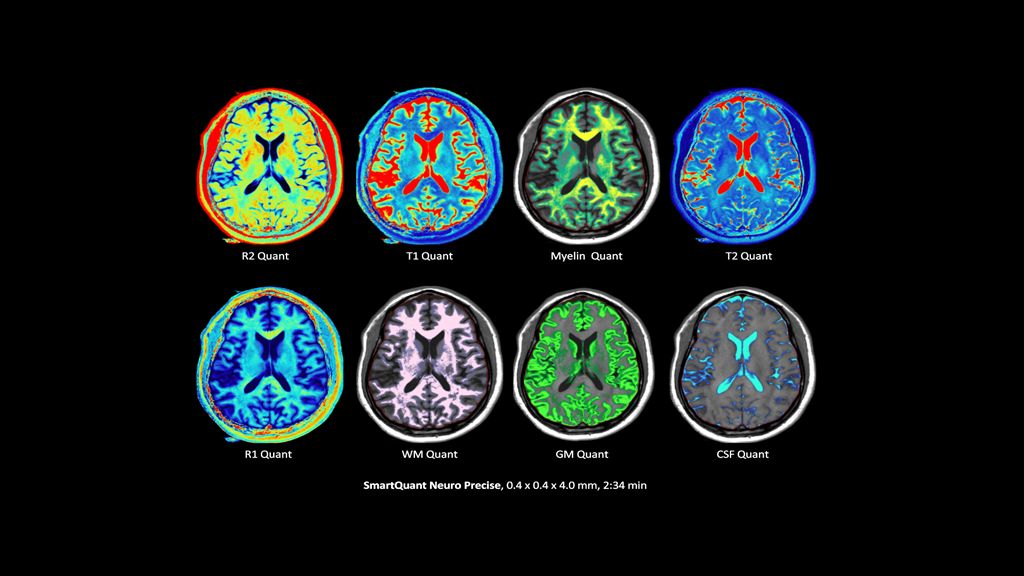

2. Reconstruction technology Compared to conventional (SENSE/ Compressed SENSE, SmartSpeed AI) imaging. Sharpness was evaluated with phantom scanning.